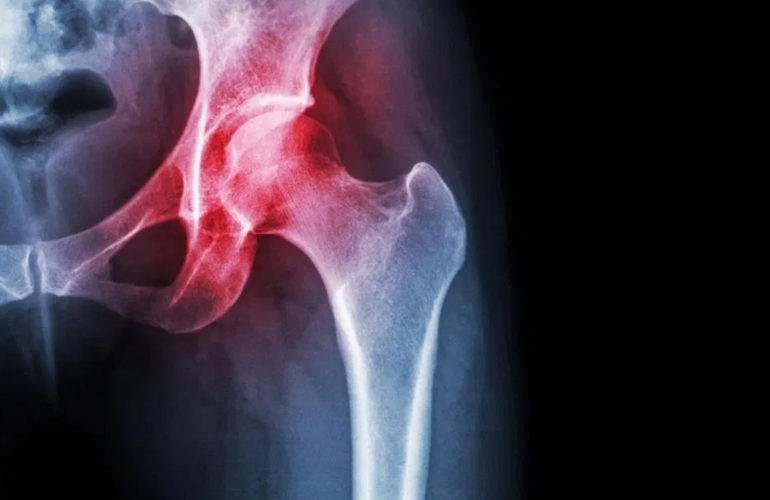

Existem duas formas distintas de Impacto Femoro Acetabular, além de um terceiro tipo, onde as duas formas estão associadas e chamamos de Tipo MISTO. Pode existir algum transtorno do colo do fêmur ou da cabeça levando a formação de uma ossificação nesta região, que se choca contra a borda do acetábulo onde está o lábio acetabular.

Esta forma de IFA é conhecida com o nome de CAM. (Figura 2 e 5) A outra forma, chamada de PINCER ou Pinçamento, ocorre quando a borda do acetábulo tem uma ossificação exagerada, que se choca contra o colo do fêmur. (Figura 3 e 6). Existem sinais radiográficos típicos desta situação, mas difíceis de serem observados por quem não está habituado.

O diagnóstico é realizado pela história e o exame clínico. Existem testes clínicos que o médico pode realizar para saber se existe impacto. Radiografias simples em diversas posições para se ver o contorno da articulação são imprescindíveis para o diagnóstico. A Tomografia Computadorizada ajuda a entender a geometria da pelve comprometida e a realizar o planejamento cirúrgico. A Ressonância Magnética com ou sem contraste é parte fundamental do arsenal de diagnóstico pois também visualiza o lábio acetabular e a cartilagem do quadril.